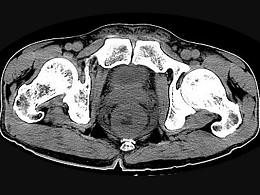

问题 男,56岁,排便形状改变,便不尽感,CT检查如图所示,下列说法正确的是 ( )

选项 A、此为直肠息肉 B、此为直肠癌 C、其表面光滑,边界清楚 D、肠腔未见狭窄 E、肠壁上有蒂状新生物

答案 B